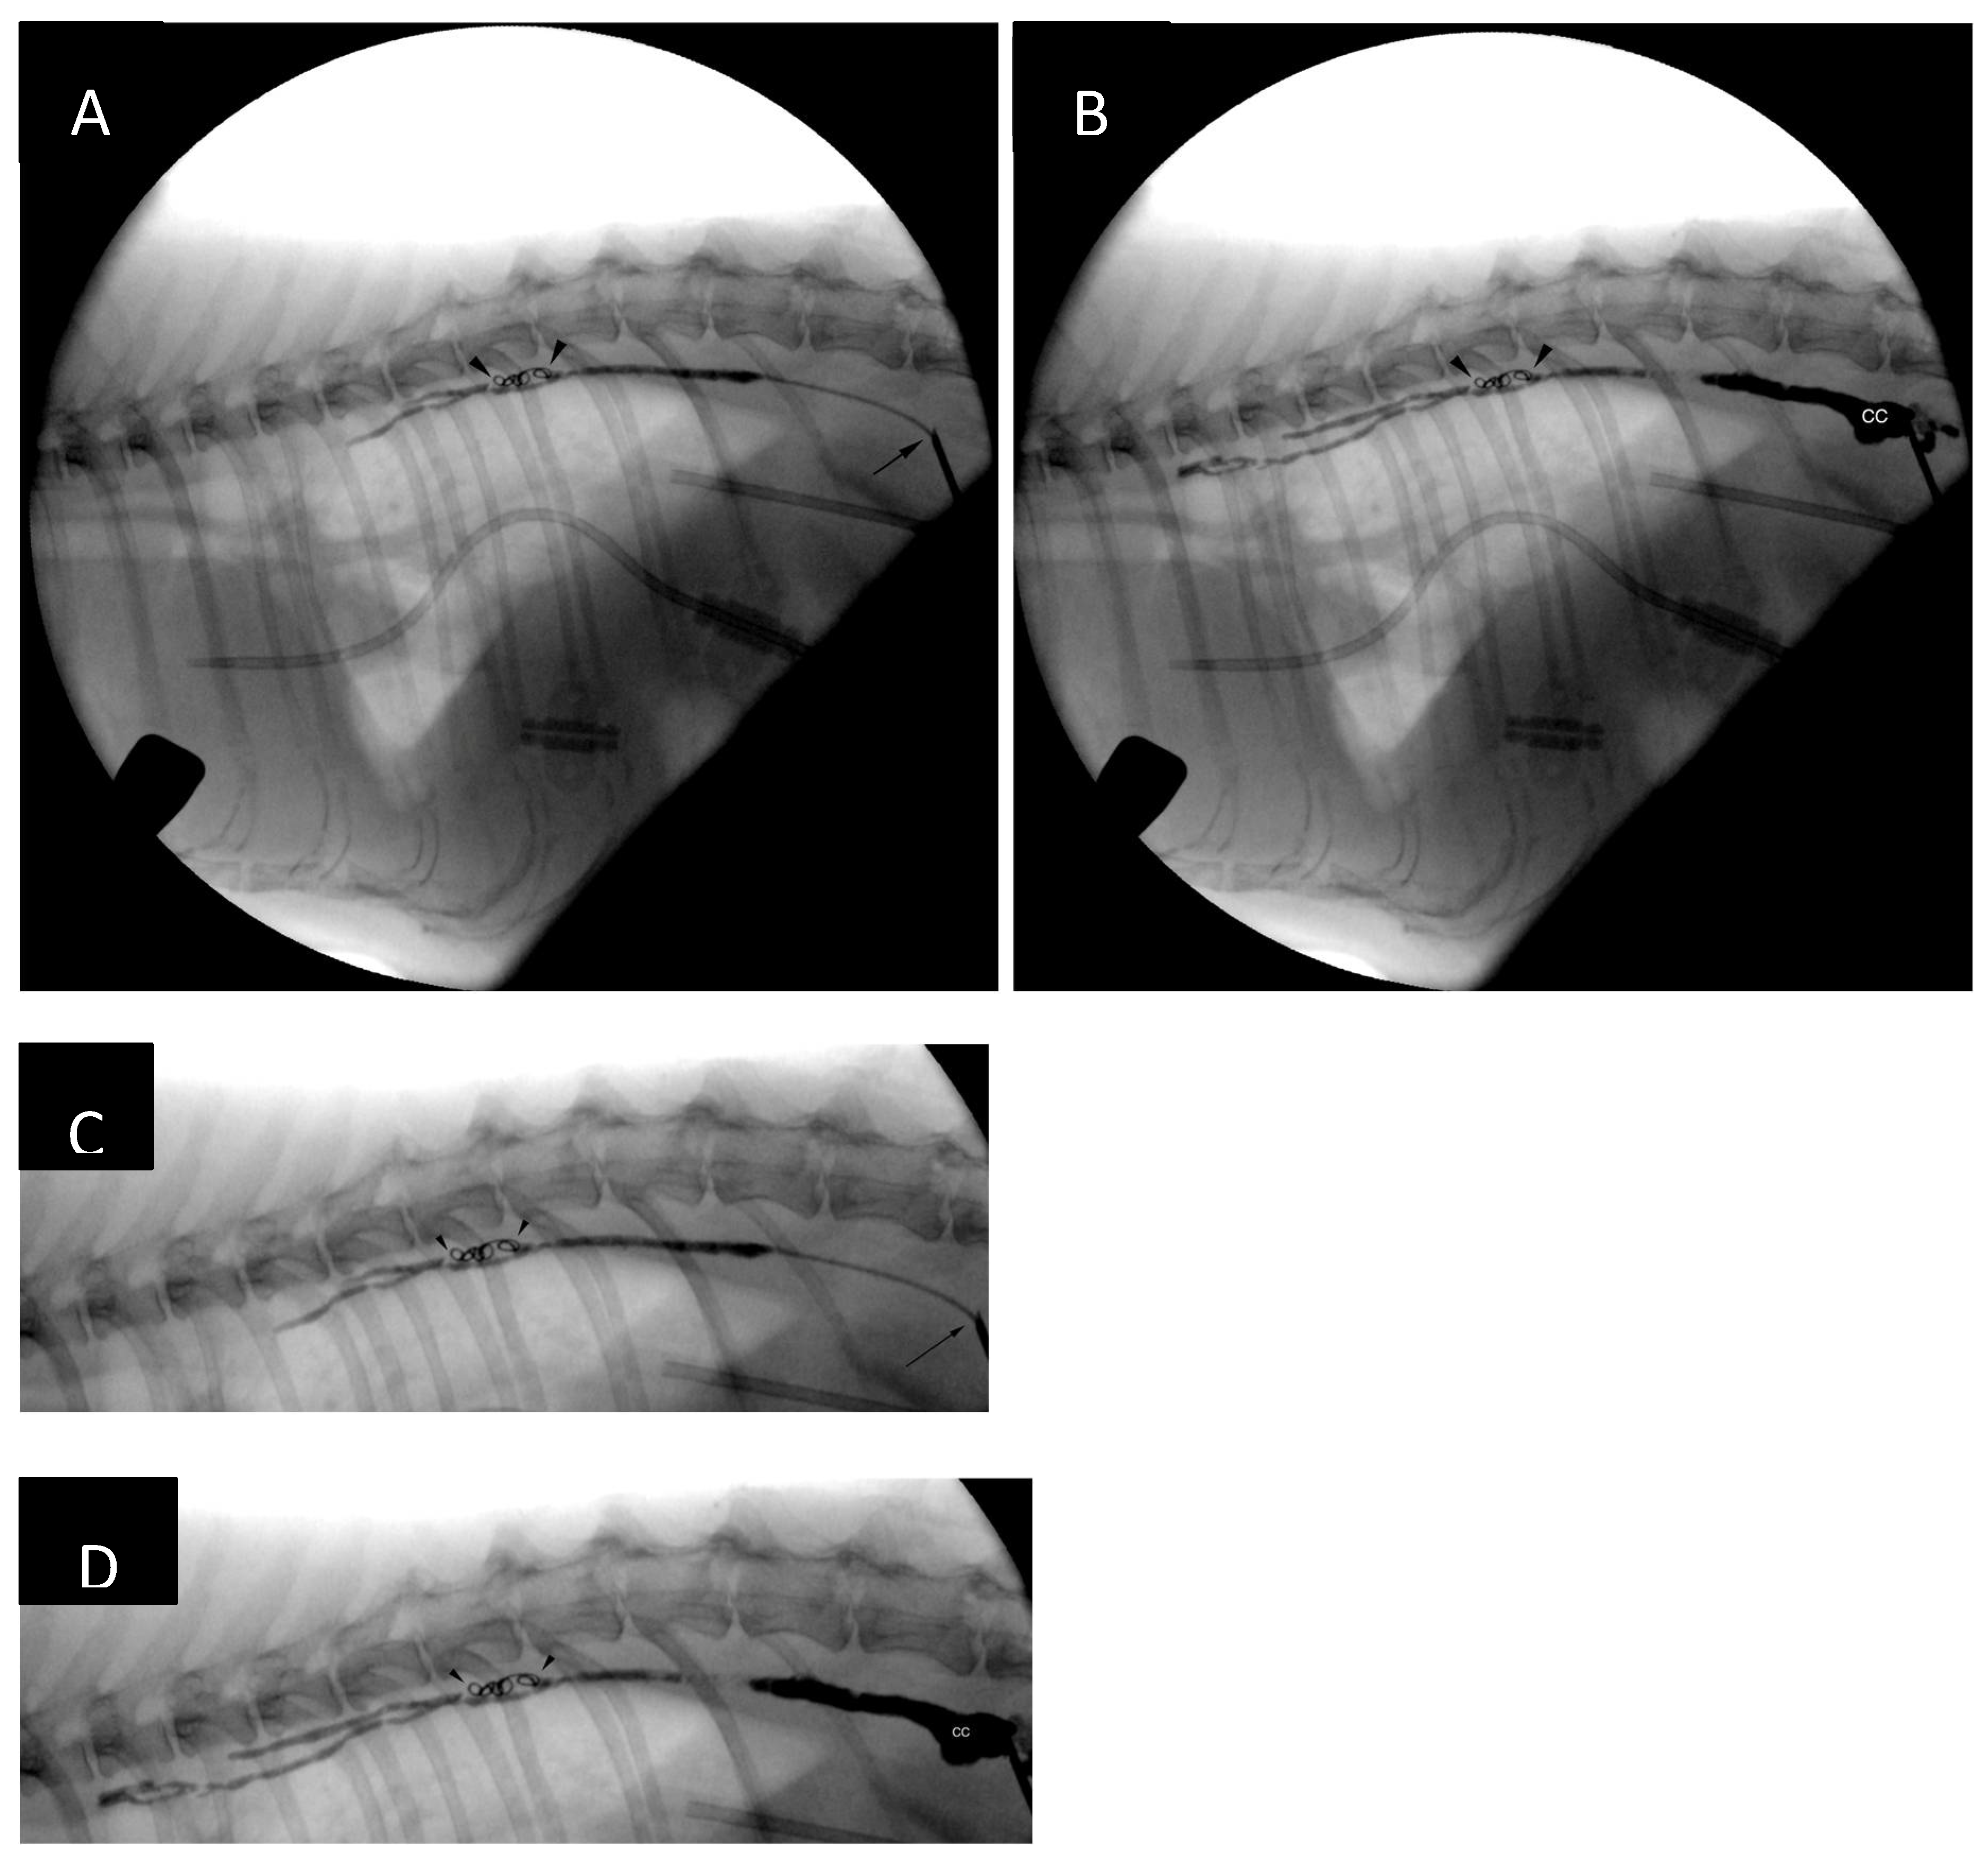

Figure 8. Early (A, C) and late (B, D) fluoroscopy frames obtained during injection of nBCA and ethiodized oil. Panels C and D are magnified versions of panels A and B, respectively. The embolic mixture does not appear to have traversed the coil mass (black arrowheads), likely due to expansion of the hydrogel. However, the adjacent thoracic duct branches have filled with glue and ethiodized oil. Compare with lymphangiograms from Figure 5 and Figure 6. The microcatheter emerging from the needle tip can be seen (black arrow on panels A and C). Most of the cisterna chyli (CC on panels B and D) has also been embolized.

After the catheter had been retracted to the lever of the cranial endplate of the T11, the image was magnified, and another lymphangiogram performed. Two 0.018-inch 2 mm x 2 cm hydrogel coils (Azur CX and Azur HydroCoil, Terumo) were deployed in the caudal thoracic duct with control lymphangiograms after each deployment. Opacification of additional thoracic duct branches could be appreciated (Figure 7). The operator's intention was to deploy an additional 0.018-inch pushable, fibered coil, unfortunately, an 0.035-inch coil was inserted into the catheter instead by mistake. This resulted in the coil being stuck in the proximal portion of the catheter. As further injections, including the injection of neat contrast (Omnipaque 300, GE Healthcare) the procedure was continued without catheter exchange. The catheter was flushed with 5% dextrose in water and embolization of the thoracic duct and cranial portion of the cisterna chyli was performed with combination of n-butyl-2-cyanoacrylate glue (Histoacryl, B Braun) and ethiodized oil (Lipiodol Ultra Fluid 480 mg I/ml, Guerbet) in 1:2 (glue-to-oil) ratio. The embolic mixture was injected under continuous fluoroscopic monitoring while retracting the microcatheter (a ‘pull-back’ technique) to obtain adequate filling of the TD and CC (Figure 7). No evidence of glue embolization into the venous circulation could be appreciated. Subsequently, the access needle was removed, and sterile dressing (Sorbact, Abigo Medical AB) applied. No skin sutures were needed. No dorsoventral imaging was performed at the time of the TDE due to limitations in room setup, although, it might have provided additional anatomical information [15].

Figure 7. (A) Lymphangiogram after repositioning of the microcatheter to the level of the cranial endplate of T11. Additional lymphangiograms after placement of the first (B) and second (C) microcoil. Opacification of additional lymphatic channels (black arrows) can be seen after coil deployment. Reflux of contrast along the microcatheter can be seen after deployment of the second coil (panel C, black arrowheads), likely due to increasing resistance to contrast medium injection.